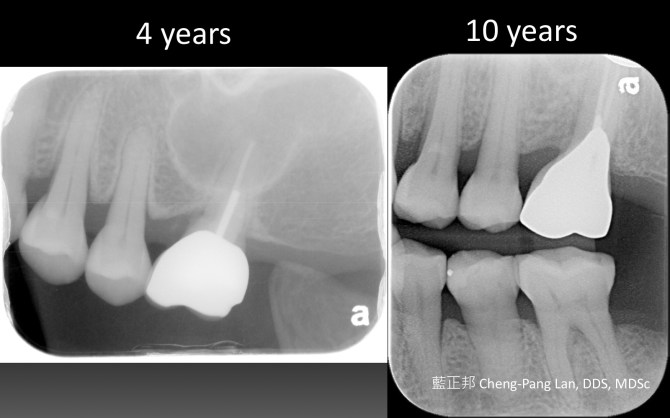

Root Amputation – Case A

This entry was posted in Treatment of Furcation-Involved Teeth and tagged Furcation, Root Amputation. Bookmark the permalink.